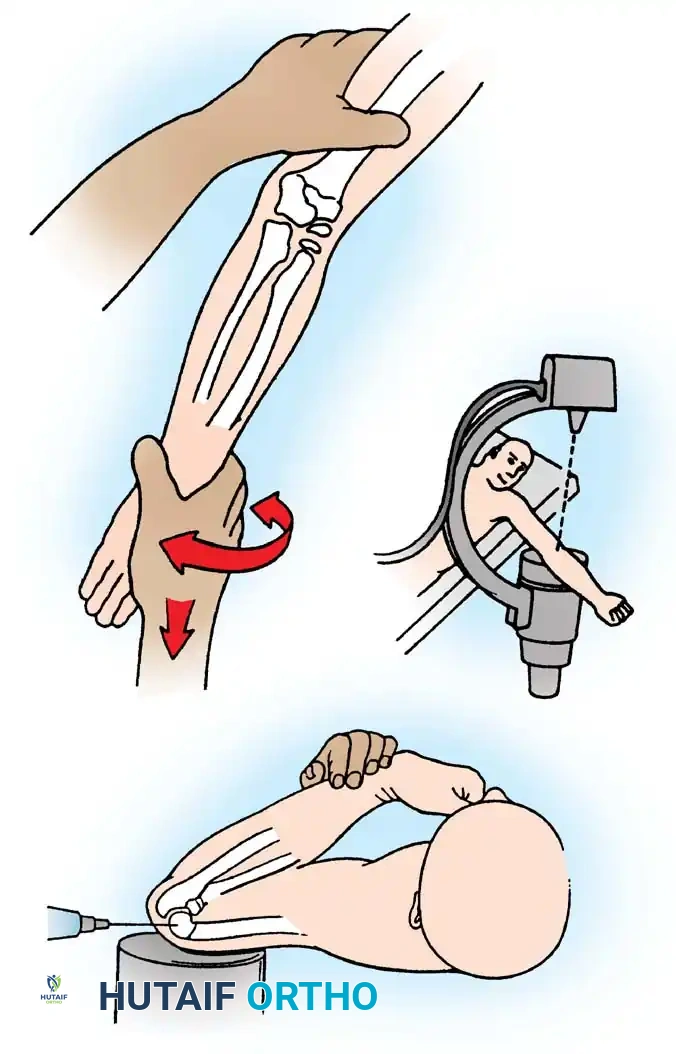

The Patterson Technique (Modified by Neher and Torch)

Fig. 33-42 Reduction technique for radial neck fractures.

- Positioning: The patient is placed supine. An assistant firmly stabilizes the distal humerus and the radius distal to the fracture site.

- Maneuver: With the elbow in full extension, the surgeon applies a strong varus stress to the elbow with one hand. This opens the radiocapitellar joint laterally.

- Reduction: Using the thumb of the opposite hand, direct lateral-to-medial pressure is applied over the tilted radial head to lever it back into anatomical alignment.

- Immobilization: The forearm is then placed in 90 degrees of flexion and pronation to lock the reduction.

Fig. 33-45 Mechanism of reduction of radial neck fracture.

PERCUTANEOUS AND INTRAMEDULLARY TECHNIQUES

When closed manipulation fails, percutaneous leverage or intramedullary pinning should be utilized before resorting to open reduction.

Percutaneous Leverage (Bernstein Technique)

Pesudo et al. and Bernstein et al. popularized the use of a percutaneous pin to manipulate the fracture fragments under fluoroscopy.

Anatomical Pitfall: During percutaneous reduction, the Kirschner wire must be introduced on the ulnar side of the radius. Introducing the wire laterally risks iatrogenic injury to the deep branch of the radial nerve (posterior interosseous nerve) as it traverses the arcade of Frohse.

The Metaizeau Technique (Elastic Stable Intramedullary Nailing)

Gonzalez-Herranz et al. and Metaizeau revolutionized the treatment of displaced radial neck fractures (O’Brien types II and III) using retrograde intramedullary pinning. This technique boasts excellent results in over 94% of cases.

- Entry Point: A small incision is made over the distal lateral radial metaphysis, taking care to protect the superficial radial nerve.

- Pin Preparation: A steel Kirschner wire or titanium elastic nail (TEN) is sharply bent at the distal 1.5 cm.

- Insertion: The wire is advanced retrograde through the medullary canal until the bent tip engages the displaced proximal epiphysis.

- Reduction: The pin is rotated 180 degrees around its long axis. The bent tip acts as a cam, elevating the radial head and shifting it medially into anatomical position beneath the lateral condyle.

Fig. 33-44 A-D, Reduction of radial head by leverage method and retrograde intramedullary pinning with Kirschner wire.